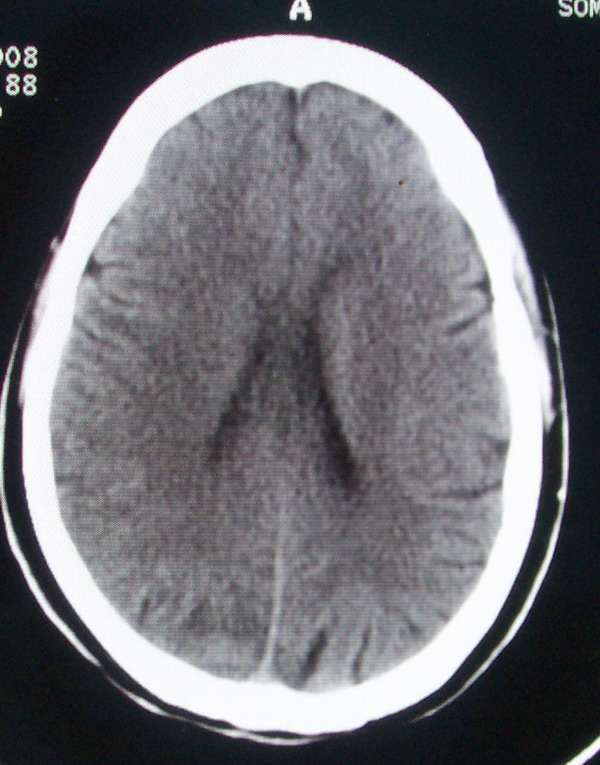

标题: CT13599:大家看是正常还是软化灶?已经重新上传 [打印本页]

标题: CT13599:大家看是正常还是软化灶?已经重新上传

考虑正常.最好有连续层面.

所给图片未见异常。

未见明确异常。